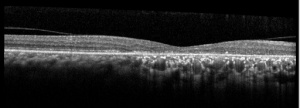

Optical Coherence Tomography (OCT)

OCT findings in AZOOR are characterized by the loss of outer retinal segments in one or more extensive zones.[14] In almost all patients with AZOOR and AIBSE, spectral-domain OCT reveals abnormalities involving the ellipsoid zone or interdigitation zone.[3] Chronically, atrophy of the RPE and thinning of the retina may be seen in the outer nuclear layer followed by thinning of the inner nuclear layer.[2][13] A trizonal appearance can also be seen on OCT. Testing was normal outside the AZOOR line (zone1). Inside the AZOOR line, multifocal material was present in the subretinal space (zone 2). Photoreceptor, RPE and choroidal atrophy are evident in zone 3).[13]